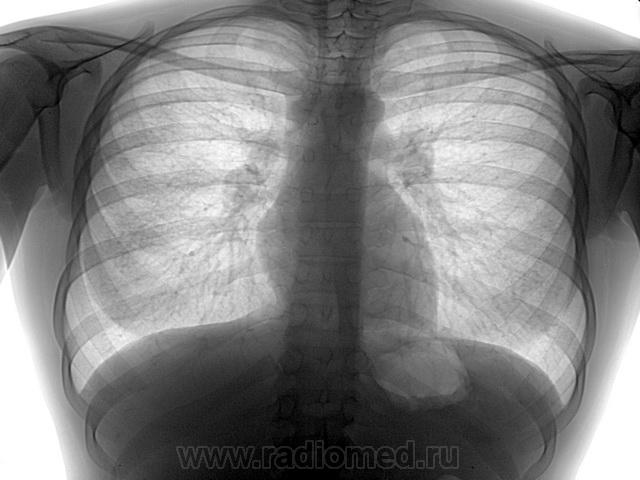

Воспалительный инфильтрат — описание болезни

Симптомы болезни Воспалительный инфильтрат

Воспалительные инфильтраты возникают как за счет контактного распространения инфекции (per continuitatum), так и лимфогенного пути при поражении лимфатического узла с дальнейшей инфильтрацией тканей. Инфильтрат обычно развивается в течение нескольких дней. Температура у больных бывает нормальной и субфебрильной. В области поражения возникают припухлость и уплотнение тканей с относительно четкими контурами и распространением на одну или несколько анатомических областей. Пальпация безболезненная или слабо болезненная.

Флюктуация не определяется. Кожные покровы в области очага поражения обычной окраски или слегка гиперемированы, несколько напряжены. Имеет место поражение всех мягких тканей данной области — кожи, слизистой оболочки, подкожно-жировой и мышечной ткани, нередко нескольких фасций с включением в инфильтрат лимфатических узлов. Именно поэтому мы отдаем предпочтение термину «воспалительный инфильтрат» перед термином «целлюлит», которым также обозначают подобные поражения. Инфильтрат может разрешаться в гнойные формы воспаления — абсцессы и флегмоны и в этих случаях его следует рассматривать как предстадию гнойного воспаления, которую не удалось купировать.

Диагностика болезни Воспалительный инфильтрат

Дифференциальную диагностику воспалительного инфильтрата проводят с учетом выявленного этиологического фактора и давности заболевания. Диагноз подтверждают нормальная или субфебрильная температура тела, относительно четкие контуры инфильтрата, отсутствие признаков гнойного расплавления тканей и резкой болезненности при пальпации. Другими, менее выраженными, отличительными признаками служат: отсутствие значительной интоксикации, умеренная гиперемия кожного покрова без выявления напряженной и лоснящейся кожи. Таким образом, воспалительный инфильтрат может характеризоваться преобладанием пролиферативной фазы воспаления мягких тканей челюстно-лицевой области. Это, с одной стороны, свидетельствует об изменени реактивности организма ребенка, с другой — служит проявлением естественного и терапевтического патоморфоза.